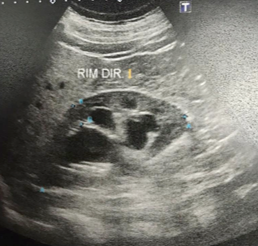

- Nefrostomia direita com punção guida por USG

- Duplo J anterógrado Esquerda